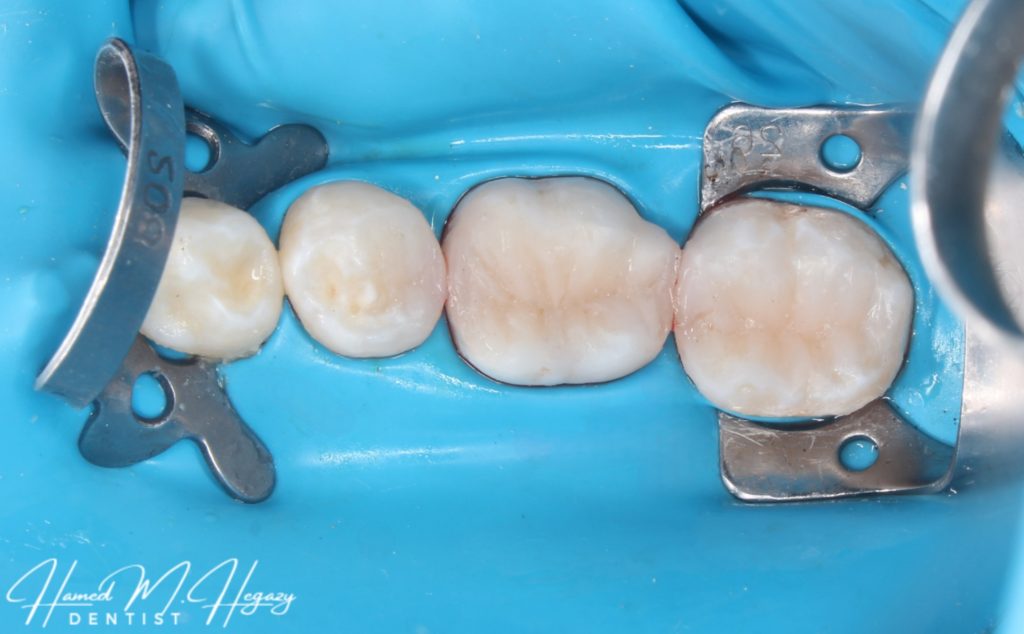

This patient came to our clinic with severe pain in the lower right side. By examination and history taking, we found the pain related to the lower right 5,6 and 7. After doing our vitality tests, we decided to do RCT for lower right 6 and then Composite restorations for lower right 5,6 and 7. We discovered an additional canal in the lower right 6 ( Middle Mesial canal ) – to become 5 in LR6 – and did class II cavity in the lower right 5 & 7.

Pre-operative